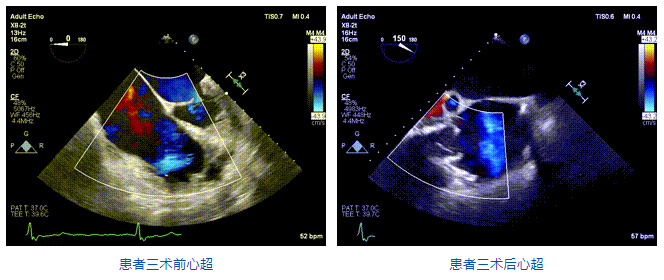

2021年12月24日,復(fù)旦大學(xué)附屬中山醫(yī)院葛均波院士團(tuán)隊(duì)成功應(yīng)用LuX-Valve Plus為一例極重度三尖瓣反流(TR)合并房顫、房缺的患者完成了經(jīng)血管三尖瓣置換術(shù),這是在前基礎(chǔ)上,本周完成的第三例經(jīng)血管三尖瓣置換手術(shù),葛均波院士、周達(dá)新教授等與心外科魏來(lái)教授、賴顥教授,心超室的潘翠珍教授、李偉教授及麻醉科的郭克芳教授共同完成了本周手術(shù),均獲得圓滿成功!患者術(shù)后超聲顯示無(wú)TR,臨床癥狀明顯改善。本周手術(shù)的成功也為L(zhǎng)uX-Valve Plus救治性臨床研究添上了濃墨重彩的一筆。

三例患者入院后,葛均波院士團(tuán)隊(duì)周達(dá)新教授、潘文志教授、張?jiān)床┦?、陳莎莎博士及心超室的潘翠珍教授、李偉教授?duì)患者的情況進(jìn)行詳細(xì)評(píng)估和討論,最終決定為三例患者選擇LuX-Valve Plus40mm、50mm和50mm型號(hào)的瓣膜進(jìn)行手術(shù)治療。手術(shù)后即刻拔除氣管插管,術(shù)后患者三尖瓣反流癥狀得到顯著改善,復(fù)查心超結(jié)果顯示人工三尖瓣瓣膜支架固定穩(wěn)定,瓣葉關(guān)閉形態(tài)未見異常,未見明顯反流。